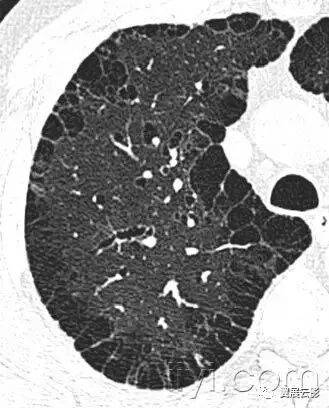

十八、小叶中心性:

解剖:小叶中心性用于描述次级肺小叶的支气管血管束中心区域。病理学上也用这一术语描述终末小支气管远端,位于呼吸性细支气管和肺泡管中心的病变。

CT:正常次级肺小叶中心的点状或者线状的密度增高影,胸膜下25px范围内最明显,代表小叶内的动脉,直径约1mm。

小叶中心性异常包括(1)结节(2)树芽征,提示小气道病变(3)由于临近间质的增厚或者浸润导致小叶中心结果更加清晰(4)小叶中心性肺气肿导致的异常低密度。

附图为小叶中心性肺气肿